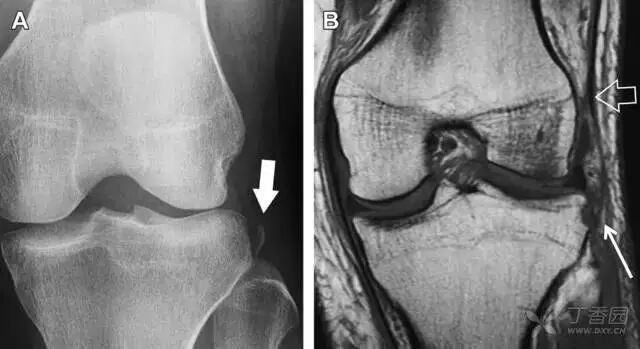

Segond 骨折

Segond 骨折是发生在胫骨平台外侧的垂直撕脱性骨折(图 4)。这种骨折在前后位 X 线片上显示最佳。

屈曲位时膝关节受到内旋暴力作用,导致皮质骨撕脱性骨折,这种骨折常发生在运动员身上。常引起股骨内髁和胫骨平台后内侧骨挫伤,75%~100% 的患者伴前交叉韧带断裂,33% 的患者伴外侧半月板损伤。

图 4 一位足球运动员的 Segond 骨折。A 正位片示关节线下方胫骨外侧皮质撕脱(箭头)。B MRI 冠状位 T1 加权像示附着于髂胫带的骨折碎片(空箭头)

反向 Segond 骨折

胫骨平台内侧皮质骨撕脱性骨折,被称为内侧 Segond 骨折或反向 Segond 骨折(图 5)。这种骨折的旋转机制与 Segond 骨折相反,该骨折与后交叉韧带断裂及内侧半月板损伤相关。

图 5 一位足球运动员的反向 Segond 骨折。A 正位片示关节线处的胫骨内侧见一细小骨折片(箭头)。B MRI 冠状位 T1 加权像示骨折片出现在内侧副韧带关节囊附着处(方框)